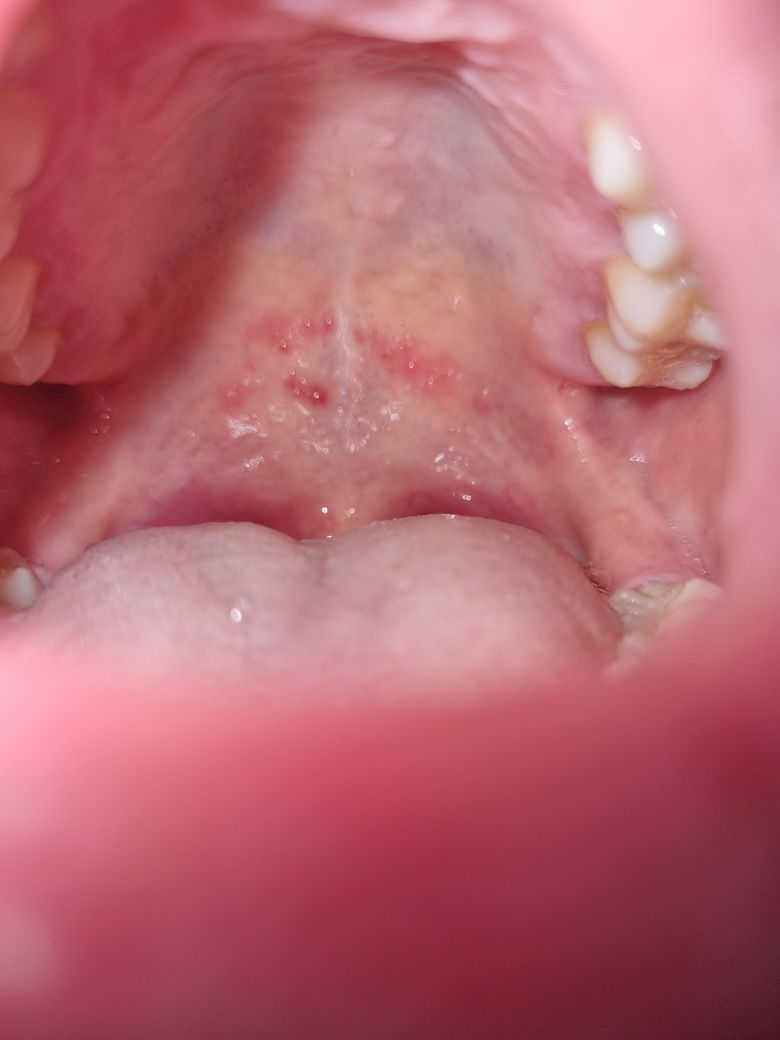

입천장에 빨간 수포 발생했는데 원인이 궁금합니다.

관계 중 구강성교도 했는데 후에 1시간 후? 입천장에 이물감이 느껴졌고, 이상하게 여겨 보니까 수포같이 올라와 있었습니다.. 여러가지 알아보니까

등 인거같은데, 일단 저는 이물감이 있고 통증은 딱히 없으며 열도 없구요. 입안에 입천장 저기 말고는 따로 난곳이 없습니다 입술주변도 없음.

하지만 목이 답답한 느낌이들게 부어있어요.

• 2번 째 사진

단순 자극에 의한 외상성 상처로 보입니다. 그냥두면 3-4일 지나면 저절로 없어집니다. 다른 증상은 아닌 것으로 추정됩니다.

입천장이 뜨거운 음식이나 자극적인 음식등에 자극을 받아서 생긴거 같으니 최대한 추가적인 자극이 가지 않도록 해주시는게 좋을것같습니다.

성병 감염과 관련된 수포일 수 있을 것 같습니다

꼭 조직검사 안하더라도 구강내과 가보시면 잠정진단 가능할 것 같습니다